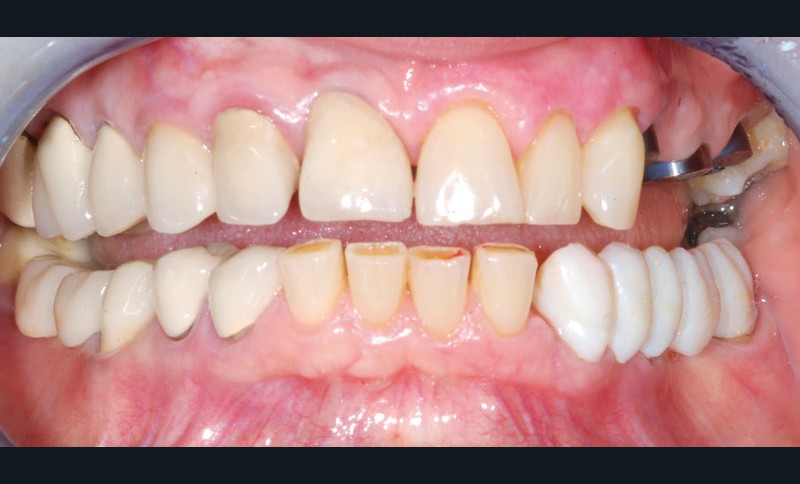

Après dépose du bridge mandibulaire et reprise du traitement endodontique, un bridge transitoire est réalisé à partir du wax-up. Une empreinte de celui-ci est faite avec Imprint™ 4 Preliminary Penta™ (3M ESPE).

L’automoulage est garni avec une résine composite (Protemp™ 4, 3M ESPE), avant ajustage et finition (roues spirales Sof-Lex™, 3M ESPE), pose du bridge transitoire.